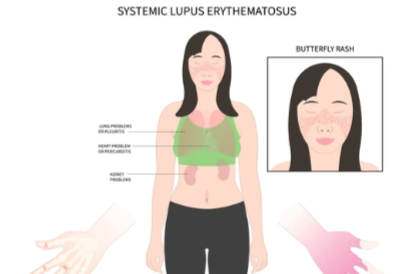

Systemic lupus erythematosus (SLE)

(Approx. ~0.05–0.1% global prevalence)

— Autoimmune connective tissue diseases where lifestyle (diet, stress, physical activity, smoking) influences systemic inflammation, comorbidities, and quality of life, though not primary disease cause.